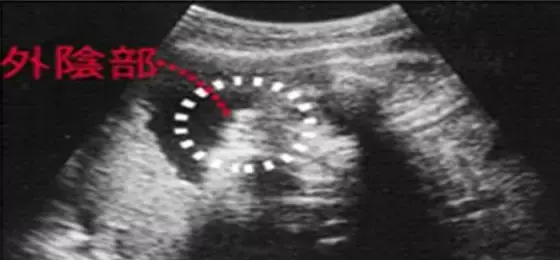

胎兒長到4.58厘米,外生殖器初步發育,如有畸形可以表現,頭顱鈣化更趨完善。顱骨光環清楚,可測雙頂徑,明顯的畸形可以診斷,此后各臟器趨向完善。手指和腳趾已經完全分開,部分骨骼開始變得堅硬,并出現關節雛形。

有人說啊,根據孕囊的形狀什么的可以看男女?

美滋滋拿到B超單,身邊的朋友或者老人會神乎其神地對著那方寸之地看了又看,根據孕囊的形狀什么的告訴你這寶寶的性別。

甚至網上啊,還煞有其事出現了教你根據孕囊判斷寶寶性別的方法:

▽

還會告訴你,這下面的三條白線是明顯的女寶特征,如果沒有看到明顯的三條白線,就看兩腿之間有沒有突出的東東,且中間有小凹槽的,就是女寶寶。???(真的假的?)